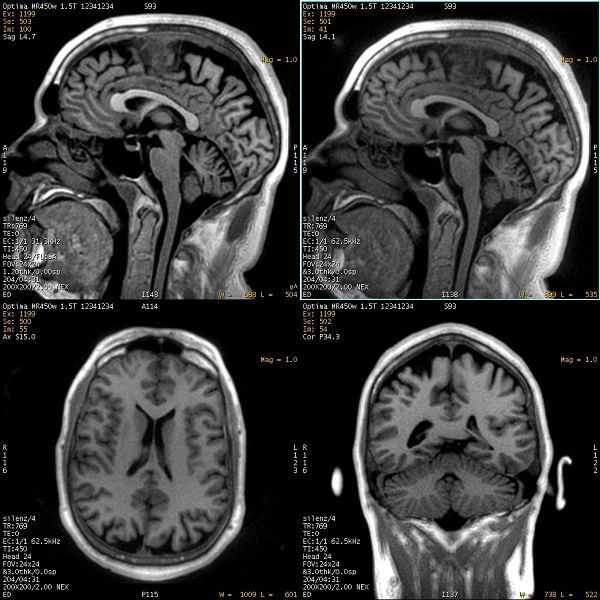

Silenz

Scanner noise is one of the top three patient complaints for an MRI scan, along with claustrophobia and loss of control. Silenz is a neurological data acquisition and reconstruction technique designed to significantly reduce the acoustic noise generated during an MR examination. Silenz generates:

The 3D data sets acquire isotropic voxels that can be reformatted into any desired scan plane.